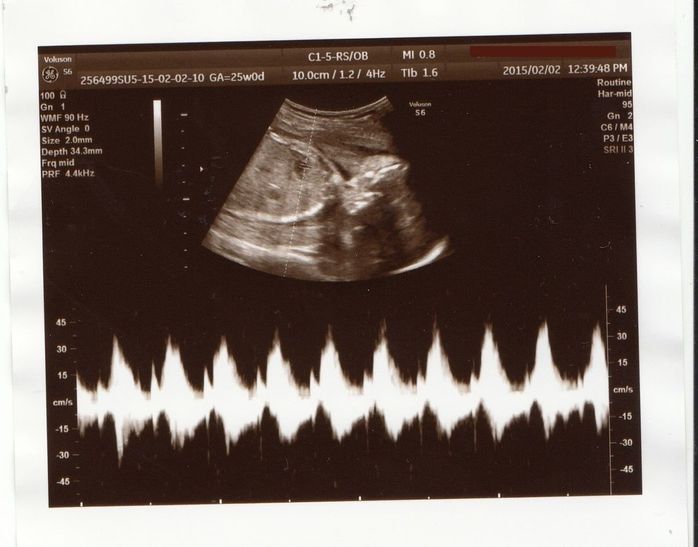

エコーに入りきらないぐらいに成長 - 妊娠25週目のエコー写真

左側の丸い輪郭が顔、その右のアゴのあたりにあるのが手です。大きくなってきて、エコーで一度に全身を確認することができません。赤ちゃんの頭の方を見てから、体に当てるプローブをずらして体の方を確認。この写真では、心拍の波形が一緒に印刷されています。この頃、つわりはおさまってきましたが、逆に食べすぎてしまい、体重が増えてしまうことを注意されました。